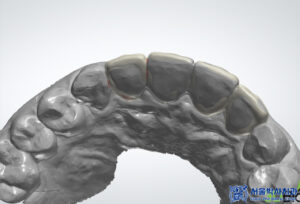

이렇게 MTA 신경치료로

앞니 자연치아를 잘 살린 이후에

원내 기공소에서 크라운

제작을 진행하였습니다.

본원 자체 운영 중인 원내기공소에서

1:1 개인 맞춤형으로

크라운을 제작하고 있습니다.

10년 차 이상의

치과기공사 실장님이 상주하며,

정교하고 세밀하게 디자인하여

보철물을 제작합니다.

또한 저작하는데 편하실 수 있도록

기능적인 면뿐만 아니라,

전체적으로 자연치아 모양과 색 등

자연스럽게 구현이 가능하도록

전문적으로 작업을 하고 있습니다.

마무리 후 사진입니다.